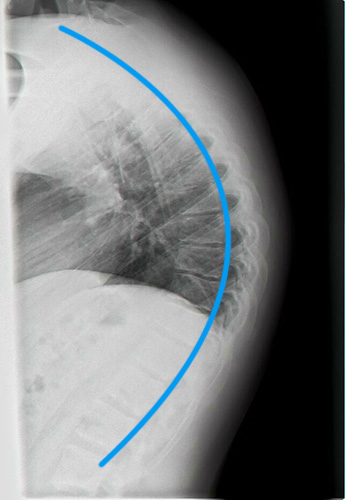

לפני ואחרי טיפול בבעיות יציבה כלליות 1

קיפוזיס שויירמן צילום לאחר 4 חודשי טיפול קיפוזיס שויירמן צילום טרום טיפול

קיפוזיס בכיפוף לפנים